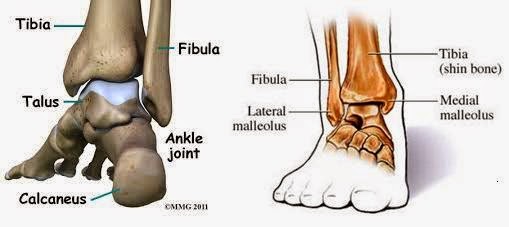

Doktor Siti: Rehabilitasi Selepas Patah Tulang Buku Lali

Doktor Siti: Rehabilitasi Selepas Patah Tulang Buku Lali